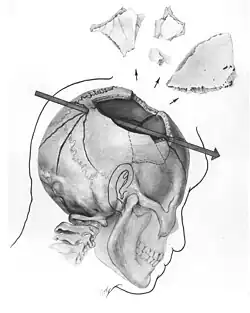

A autópsia foi realizada por três médicos da Marinha com trinta oficiais militares como testemunhas. Dois agentes reformados do FBI que estavam presentes declararam que Kennedy tinha uma grande ferida no lado direito da cabeça, outra de aproximadamente 14 cm acima do lado direito da coluna, e uma terceira ferida no lado anterior da garganta perto do limite inferior do pomo de Adão (a Comissão Warren deu a mesma informação). O relatório do FBI sobre a autópsia foi realizado pelos agentes especiais Sibert e O'Neill.[18] Várias fotos e radiografias foram feitas durante a autópsia (algumas delas desapareceriam dos relatórios oficiais).

Diagrama feito para o Comitê da Câmara mostrando a trajetória da bala no crânio do presidente Kennedy. A ferida posterior corresponde à pequena ferida de entrada acima. Os fragmentos de crânio são mostrados explodidos para fins ilustrativos; a maioria ficou presa ao crânio por retalhos de pele, que estão sendo puxados para a frente pela mão enluvada no desenho feito a partir de uma ilustração da autópsia. |

Uma fotografia da cabeça do presidente, tirada durante uma autópsia no Hospital Naval de Bethesda; a natureza da lesão pode corresponder ao uso de uma bala com efeito explosivo, a chamada "Dum Dum".[19] | |||